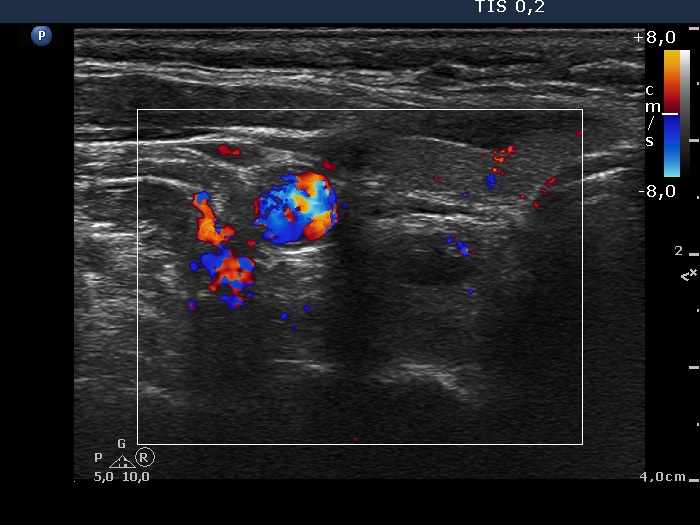

Ultrasonography. The thyroid was minimally hypoechoic and had several insignificant hypoechoic lesions. There was a solid-cystic mass dorsal to the lower pole of the right lobe.